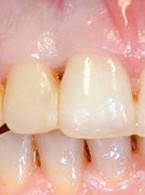

Pokrycie mnogich recesji dziąsłowych

metodą płata przesuniętego dokoronowo z wykorzystaniem przeszczepu podnabłonkowej tkanki łącznej i kolagenowego materiału ksenogennego po wcześniejszej rekonstrukcji połączenia szkliwno-cementowego - opis przypadku